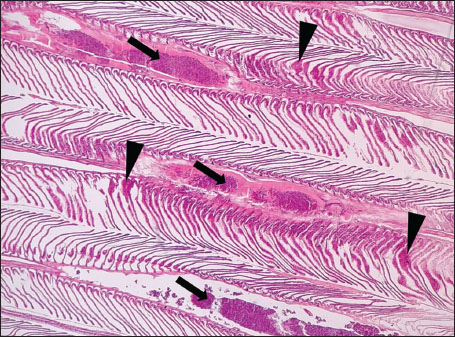

ABSTRACTBackground: The Mediterranean Sea has undergone significant ecological changes in recent decades, partly due to the introduction of non-native species. Lagocephalus sceleratus is an invasive Lessepsian species widely distributed in the Mediterranean, increasingly abundant along the Libyan coast, and potentially exposed to chronic environmental stressors. This species represents an important model for baseline pathological assessment in newly colonized marine environments. Aim: This study provides a descriptive histopathological assessment of kidney and gill tissues in adult L. sceleratus to document baseline tissue alterations without inferring direct environmental or pollution-related causation. Methods: A total of 150 adult specimens were collected from four Libyan coastal locations. Tissues were processed using standard histological techniques and evaluated semi-quantitatively (+, ++, +++) for lesion severity. Lesion severity grades were converted into ordinal numerical data and summarized using descriptive statistical approaches only. Results: Kidney tissues exhibited tubular degeneration, Bowman’s capsule dilatation, vascular congestion, extensive melanomacrophage centers (MMCs), and inflammatory lesions. Gill tissues showed disorganization of secondary lamellae, epithelial hyperplasia, edema, aneurysmal dilatations, vascular congestion, and MMC proliferation, some of which were associated with histologically observed parasitic structures. Conclusion: The observed alterations represent descriptive baseline tissue changes and should not be interpreted as direct evidence of pollution or specific environmental stressors. These findings provide reference data for future comparative pathological and ecological studies. Keywords: Lagocephalus sceleratus, Kidney, Gills, Histopathology, Melanomacrophage centers, Invasive species, Mediterranean Sea. IntroductionIn recent decades, the Mediterranean Sea has undergone profound ecological changes driven by the arrival and establishment of non-native marine species. Among these, Lagocephalus sceleratus has emerged as one of the most impactful Lessepsian migrants, due to its rapid geographic expansion, high ecological adaptability, and the presence of the potent neurotoxin tetrodotoxin in its tissues. This species has been widely documented to alter local fish communities, affect fisheries, and pose public health risks, making it an important target for biological and environmental assessment across the region (Katikou et al., 2022; Christidis et al., 2024). Fish are widely recognized as sensitive biological organisms in aquatic ecosystems, particularly in coastal habitats that are exposed to anthropogenic pressures such as industrial effluents, agricultural runoff, and untreated wastewater (Pinna et al., 2023). Among fish organs, the gills and kidneys are commonly regarded as sensitive to environmental stress, as they respond to physiological and pathological changes under environmentally suboptimal conditions. The gills, due to their large surface area and continuous exposure to surrounding water, are often the first tissues to exhibit structural alterations when fish encounter pollutants (Shahid et al., 2022). Histopathological changes in gills observed in polluted environments include epithelial lifting, lamellar fusion, hyperplasia, increased mucous cell density, and focal necrosis, which collectively reflect early physiological stress and potential compromise of respiratory function (Osman, 2010; Shahid et al., 2022). Similarly, the kidneys play crucial roles in osmoregulation, excretion of metabolic waste, and detoxification, making them highly vulnerable to chronic or systemic toxic effects (Wahidi et al., 2025). Documented renal lesions associated with chemical exposure include tubular deterioration, glomerular shrinkage, interstitial edema, and infiltration of inflammatory cells. These structural alterations often coincide with underlying biochemical disruptions, such as oxidative stress, impaired detoxification pathways, and activation of apoptotic mechanisms (Bernet et al., 1999; Authman, 2015). Despite the growing body of research on the ecological and toxicological implications of L. sceleratus, detailed histopathological assessments of this species remain scarce, especially in the southern Mediterranean basin, where environmental conditions and pollution profiles may differ from those in other regions. To date, detailed tissue-level studies of L. sceleratus from the southern Mediterranean are lacking, which limits the understanding of how this invasive species responds physiologically to local environmental stressors (Shakman et al., 2019; Ulman et al., 2021; Mohmmed et al., 2023). Accordingly, the present study aims to provide a comprehensive descriptive evaluation of histopathological changes in the kidneys and gills of L. sceleratus. The study is designed as a baseline histopathological assessment, focusing on tissue-level alterations without establishing causal links to environmental pollution or physicochemical stressors. By documenting structural aberrations and pathological features, this study contributes reference data for future monitoring and comparative studies in Mediterranean coastal ecosystems. Materials and MethodsSample designA total of 150 adult specimens of L. sceleratus, including both sexes, were collected from four Libyan coastal locations: Talamitha (n=39), Susah (n=34), Ain El-Ghazala (n=30), and Khalij Al-Bambah (n=47). Fish ranged in total length from 51 to 66 cm and in weight from 1.5 to 3.5 kg. Only apparently healthy adults were included, while juveniles were excluded to avoid age-related histopathological variation. Sampling was conducted opportunistically with assistance from local fishermen. All specimens were collected within a comparable seasonal window to minimize seasonal histopathological variability. Sex was recorded when possible; however, sex-based histopathological comparisons were not performed, as this was beyond the descriptive scope of the study. Fish were transported on ice at +4°C and examined in the Pathology Laboratory, Faculty of Veterinary Medicine, Omar Al-Mukhtar University (Mohmmed et al., 2023). Specimens were collected from a range of depths (0.5–70 m), with the majority from shallow waters (<10 m) and a subset (approximately 50 fish) from deeper locations (>30 m). Environmental physicochemical parameters such as temperature, salinity, and dissolved oxygen were not measured; therefore, no direct associations between histopathological findings and environmental variables were assessed. Tissue processing and histopathological examinationTissue specimens were fixed in 10% neutral buffered formalin for 24 hours. Following fixation, the samples were transferred to 70% ethanol for storage at room temperature. Subsequently, the tissues were processed for routine histopathological examination following standard procedures (Paul and Chanda, 2017). Paraffin embedding was performed, and 5 µm-thick sections were prepared using a microtome. Sections were stained with hematoxylin and eosin (H&E) and examined under a light microscope. Photomicrographs of representative lesions were captured using a high-resolution digital camera. Histopathological alterations were evaluated using a semi-quantitative scoring system adapted from Hose et al. (1996), Moshaie-Nezhad et al. (2021), and Alshailabi et al. (2023), where lesion severity was graded as mild (+), moderate (++), or severe (+++). Lesion severity grades (+, ++, +++) were converted into ordinal numerical values (1–3) for descriptive summarization of lesion severity. Due to the descriptive baseline nature of the study and the absence of a reference control group, inferential statistical comparisons were not emphasized or applied. Lesion severity scores were therefore summarized descriptively to avoid overinterpretation of the findings. Scoring was performed independently by two experienced observers, and representative lesions were confirmed across three sections per organ to ensure consistency. Tissues with visible parasitic structures were described separately from non-parasitized tissues to avoid conflating parasite-associated lesions with non-specific tissue alterations. The functional implications of the observed lesions were interpreted in accordance with Flores-Lopes and Thomaz (2011). Ethical approvalAll animal experiments conducted in this study were approved by the Ministry of Higher Education & Scientific Research and the Libyan National Committee for Biosafety & Bioethics, Libya. All procedures were performed in accordance with the relevant ethical guidelines, with session number 21/CH/25, dated 26/05/2021. ResultsHistopathological examination of the kidneyHistopathological examination of the kidney tissues of L. sceleratus revealed multiple alterations. Prominent melanomacrophage centers (MMCs), necrotic areas, dilatation of Bowman’s capsules, and vacuolar degeneration were observed (Fig. 1), associated with interstitial lymphohematopoietic tissue (Fig. 2). Dilated and congested blood vessels and extensive MMCs were also noted (Fig. 3). Renal degeneration surrounding lymphohematopoietic tissue, large clusters of MMCs, and thickened, congested vessel walls within fibrotic areas were evident (Fig. 4). Atrophic renal degeneration with necrotic and vacuolar changes was observed (Fig. 5). Severe inflammatory infiltration of lymphatic cells and granulomas with necrotic centers, surrounded by fibrous tissue, was detected (Figs. 6–7).

Fig. 7. Histopathology of the kidney in an adult L. sceleratus showed the atrophic renal degeneration (stars), dilatation of Bowman’s capsules (thick arrows), and a granuloma (head arrow). ×400 H&E. Histopathological examination of the gillsThe gill sections of adult L. sceleratus exhibited multiple structural alterations. Secondary lamellae showed marked disorganization, while gill filaments displayed club-shaped deformities and occasional aneurysmal dilatations (Fig. 8). Vascular congestion with telangiectatic changes and proliferation of MMCs were also observed (Figs. 9–10). Edematous changes in primary lamellae, separation of the epithelial layer, lamellar aneurysms, and epithelial hyperplasia were documented (Figs. 10–11). Focal damage to secondary lamellae, disruption of lamellar architecture, presence of lamellar aneurysms, and unidentified parasitic structures were observed (Fig. 12). Pronounced vascular congestion and dilatation of lamellae due to red blood cell accumulation were noted (Fig. 13).

Fig. 13. Histopathology of the gills in an adult L. sceleratus showing congestion and telangiectasia of gill filament vessels (thick arrows) and lamellar dilation due to RBC accumulation (head arrows). ×40 H&E. Gill lesions were described separately for tissues with visible parasites and those without parasitic structures to improve interpretative clarity. Summary of lesionsHistopathological alterations in both kidney and gill tissues were classified using a semi-quantitative scoring system (+, ++, +++) (Fig. 14).